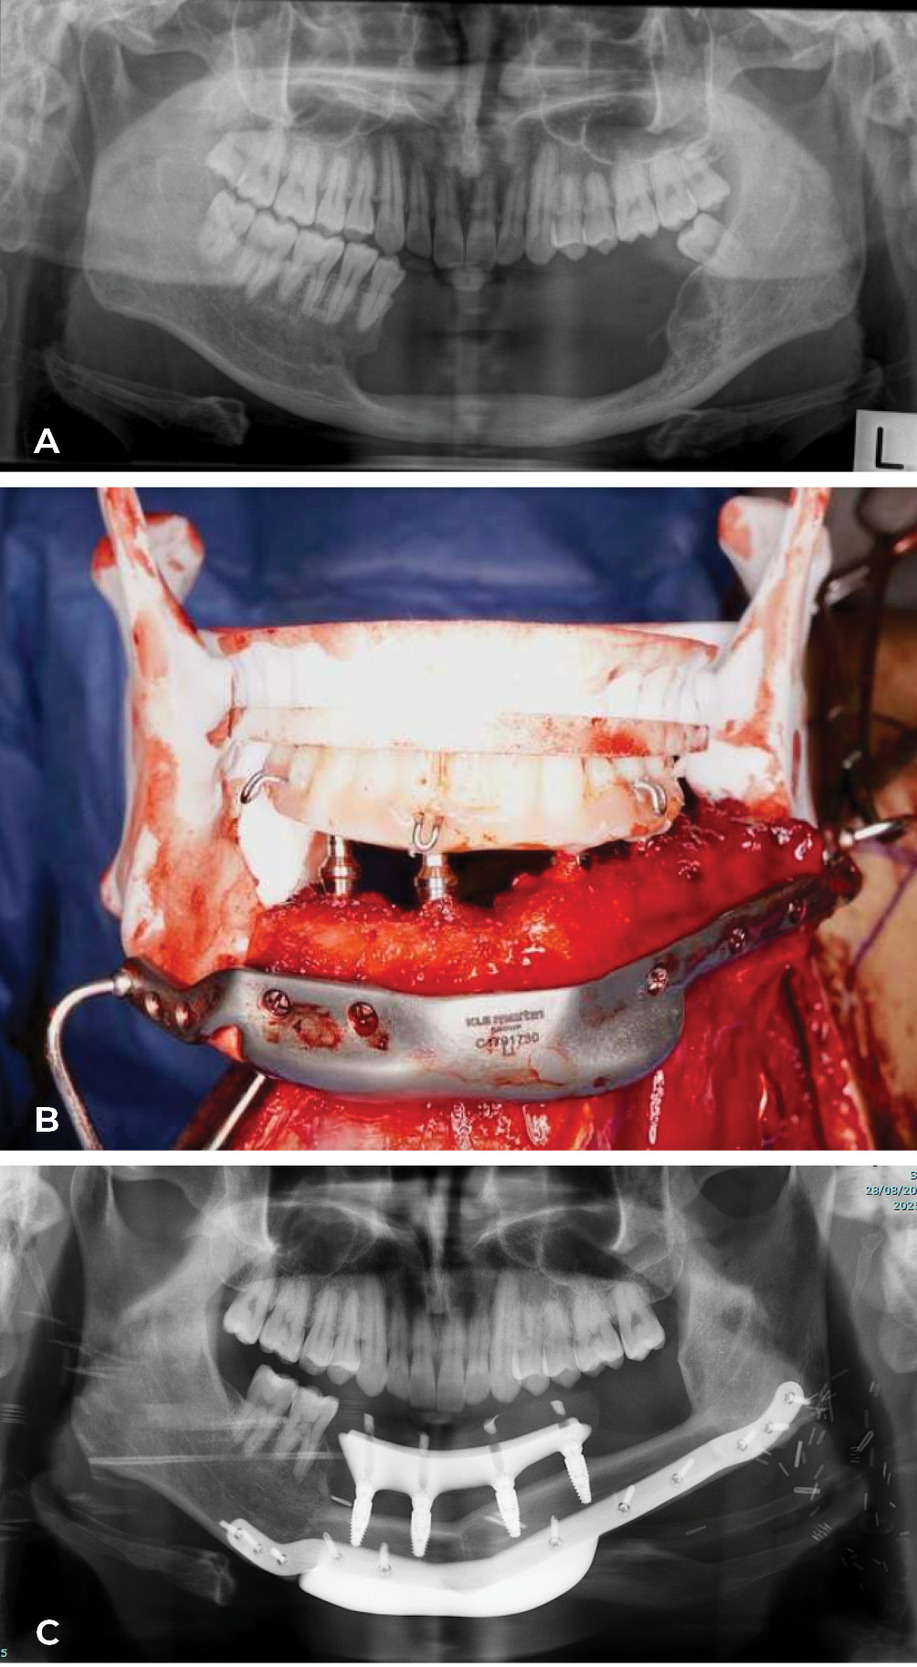

- The jaws: initially we confined the fibula to reconstruction of the bony arch of the mandible or maxilla. A range of acrylic models were used to match the shape of the removed or missing jaw segment shown in Case 5. Two bone wedges were removed from the inner surface of the fibula with an intermediate segment to recreate the chin and fixed with a single mini plate (Figure 24 and Figure 25).

Today the ‘Model T Ford’ has changed shape at the Royal Melbourne Hospital. The computer (3D printing) is used to generate a replica of the fibula, selected after angiography, plus the patient’s jaw segment to be removed. Key osteotomies, with their site and angle, are designed on the fibula replica to reconstruct the shape of the jaw. In a case Ian watched in theatre, the fibula reshaping was done and fixed with plates while still attached in the leg. The fibula was detached, fixed in the mandible and dentures inserted at predetermined sites to match the occlusion of the upper jaw. The patient went to theatre with a tumour in the jaw and woke with a new set of teeth! A case done by Anand Ramakrishnan, Head of Plastic and Reconstructive Surgery and the team at the Royal Melbourne Hospital, is shown in Case 6 (Figure 26 and Figure 27). Combined with maxillofacial and oncological surgeons they now provide four separate teams a week at the Royal Melbourne Hospital to treat facial malignancy. In the last 10 years their total of fibula jaw reconstructions is 198.